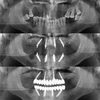

زراعة الفم والأسنان